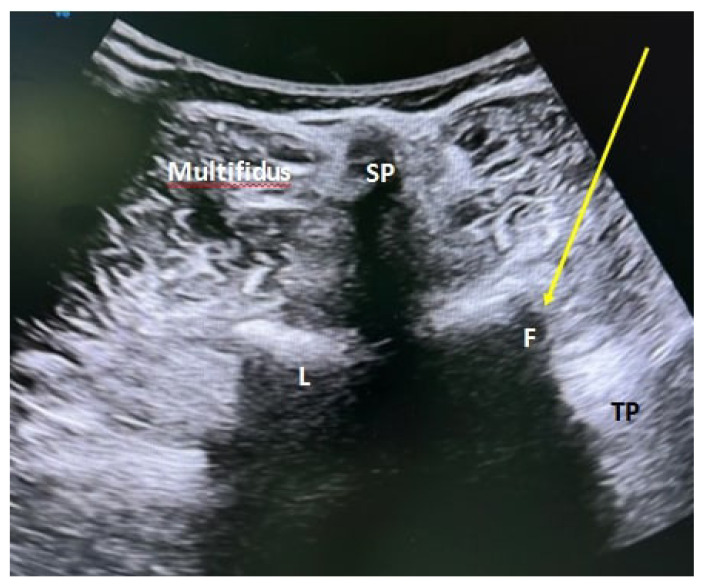

Materials and methods: A total of 50 patients were randomly divided into 2 groups of 25 patients each underwent PFOI by USG or TFESI via fluoroscopy. Pain intensity was assessed with visual analogue score (VAS), disability with Oswestry disability index (ODI), and QoL with short form-36 (SF-36), before treatment, at the 2nd week, 1st month, and 2nd month, after treatment.

Abstract Image